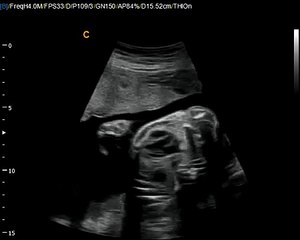

12 Weeks Pregnant Gender Determination Ultrasound

85 chance its a girl - determined at the end where the cursor is pointing\rbr\rbr*confirmed 100 at 20-week ultrasound